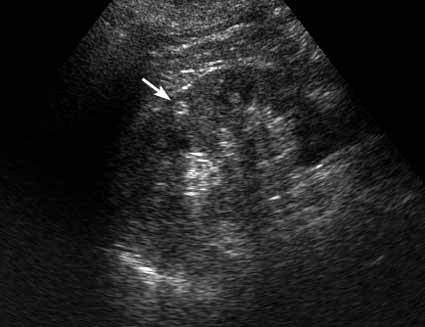

PS. Кстати, а что это у нее рядом с правым надпочечником?

Область правого надпочечника

PS. А надпочечник в срез не попал. Что-то, возможно, прилежит к области проекции надпочечника и к верхнему полюсу почки.

PS А где там есть надпочечник - не вижу.